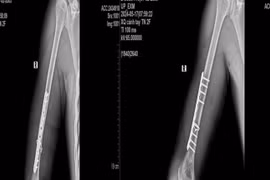

1 tuần 3 trường hợp gãy xương cánh tay từ trò chơi vật tay

Có những trường hợp nhập viện trong tình trạng gãy nham nhở, khó đưa xương về vị trí ban đầu, tổn thương các dây thần kinh quay, trụ và mạch máu lân cận.

Trong lúc thi vật tay cùng bạn bè, nam thanh niên 18 tuổi bất ngờ nghe thấy một tiếng “rắc” vang lên, kèm theo cảm giác đau dữ dội.